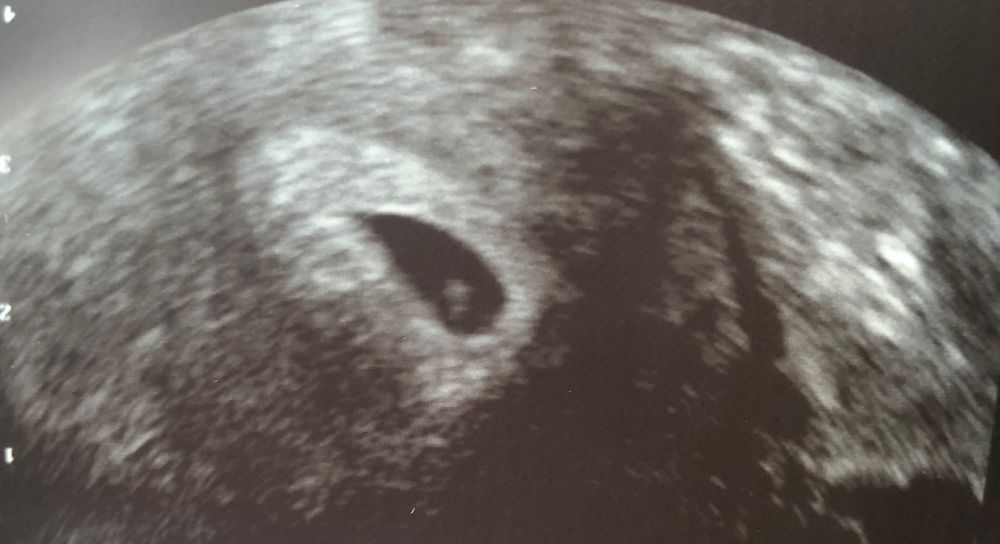

6 неделек ровно. Первое УЗИ

Хгч на 25 дпо - 6677.

сегодня сходила на первое узи (27 дпо), нас нашли ❤️

ПЯ -13,8 мм

КТР-3,9 мм

Ж мешочек -3 мм

СБ + ❤️❤️❤️

очень напугана гематомой на узи (ретрохориональная гематома ) в стадии регресса. Врач сказала лежать 2 недели и начинать пить дюф по 3т в день.